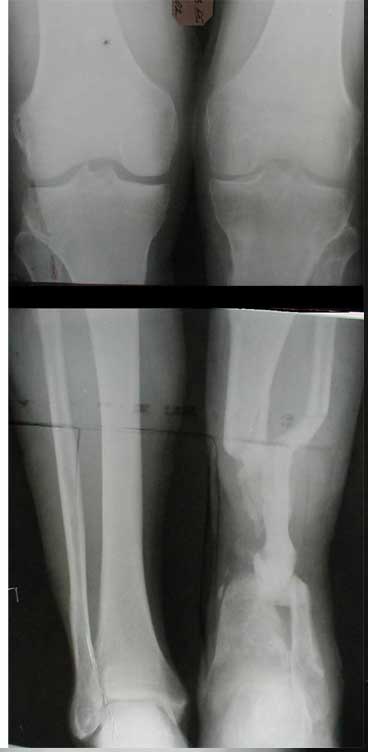

В приложении - моё наблюдение (возможно, уже представлял, тогда

извините).

Нога попала в пресс.

Ко мне больной попал черз 1,5-2 года после травмы и нескольких

операций с синегнойной инфекцией на всю голень. Меня пригласили на консультацию

насчет ампутации.

Лечил я его месяцев 8.

Малоберцовка полностью перестроилась, нога опороспособна.

При ходьбе на дальние расстояния пользуется тростью.

Осталась трофическая язва, периодически закрывается.